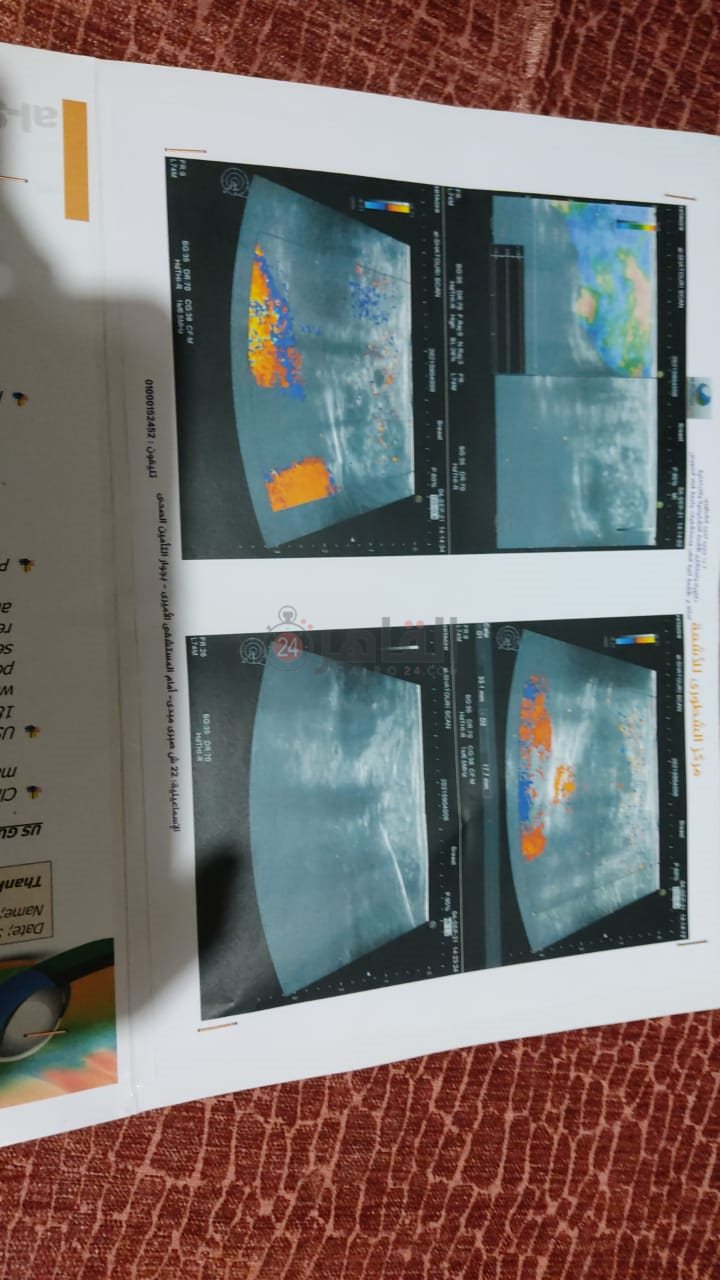

تقول أمل عبدالله عبدالرازق، في حديثها لـ القاهرة 24، إنها أصيبت بمرض سرطان الثدي منذ سنوات، ولا تزل تبحث عن علاج دون جدوى، لافتةً إلى أنها طرقت البواب حتى انتهى بها المطاف في مسكن متواضع بالإيجار بعزبة التب، التابعة لدائرة مركز ومدينة الحسينية بمحافظة الشرقية؛ بعدما طردها زوجها من منزلها هي وطفليهما لتعيش على نفقه أهل الخير.